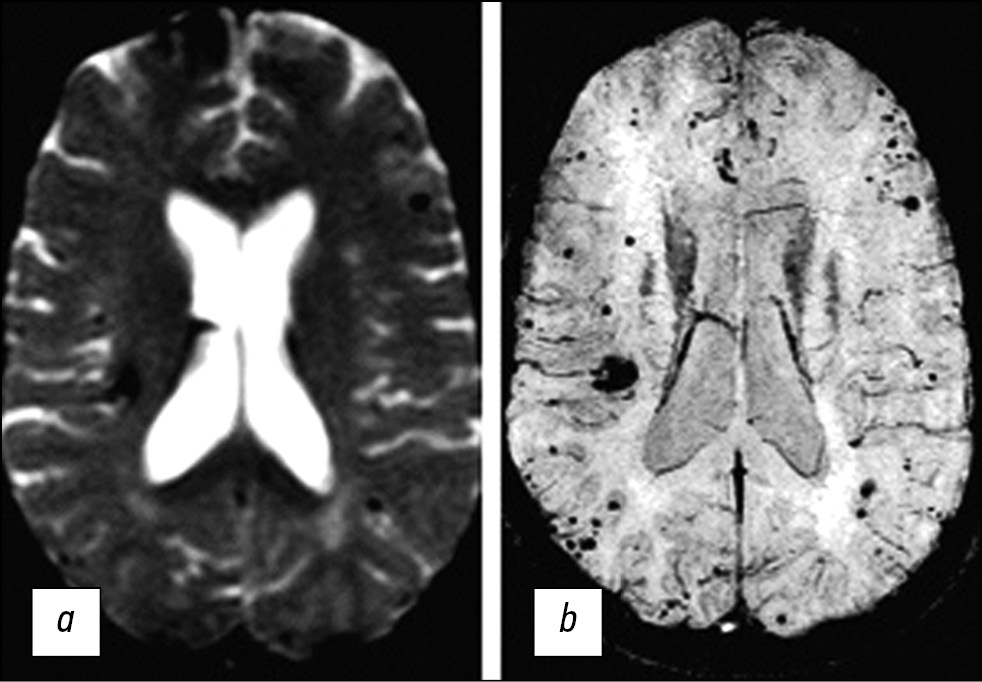

In general, T2*GRE sequences can be utilized to reveal the “blooming” effect of hemosiderin and increase the sensitivity of CM detection. SWI sequences, especially with a magnetic field level of 3 T, can be used to identify multifocal lesions in the case of familial CMs that cannot be identified with T2*GRE images (Fig. 4) [27]. With such approaches, the diagnostic capabilities of MRI significantly increase.

Fig. 4. MR images of the brain in the axial view in the T2*GRE (A) and SWI (B) modes. SWI images can reveal additional CM lesions not visible in the T2*GRE.